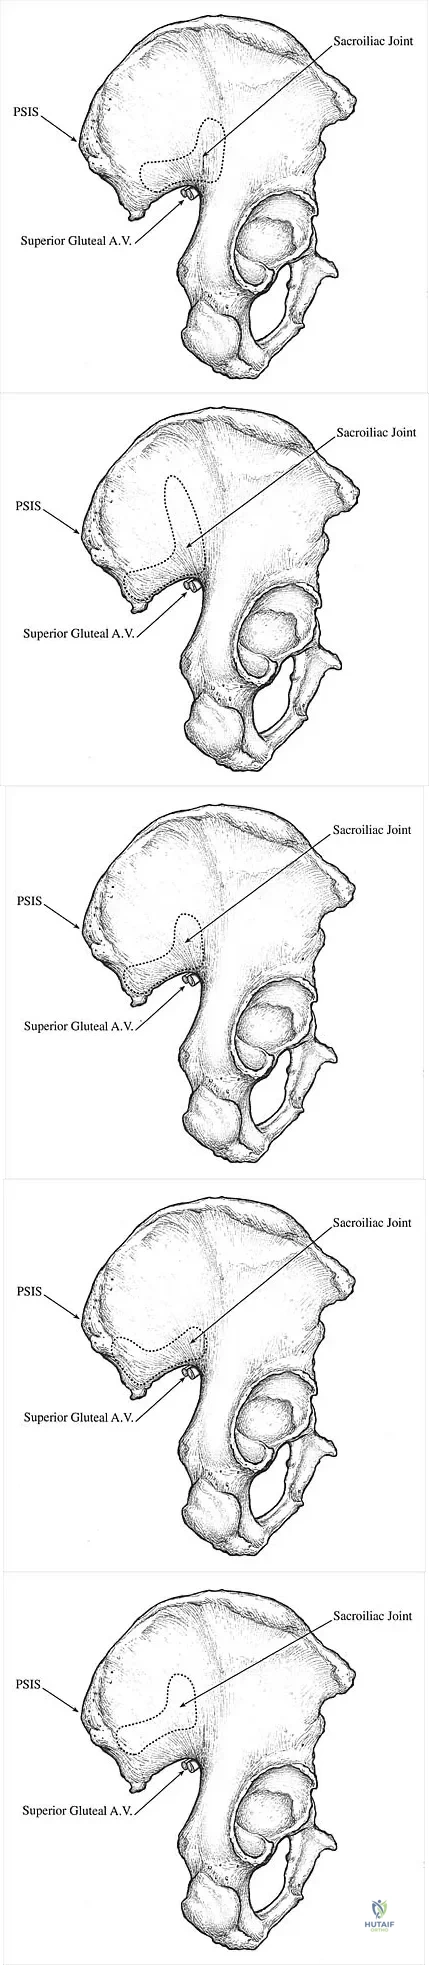

Which of the following illustrations shown in Figures 21a through 21e correctly shows the projection of the sacroiliac joint on the outer table of the ilium?

Explanation